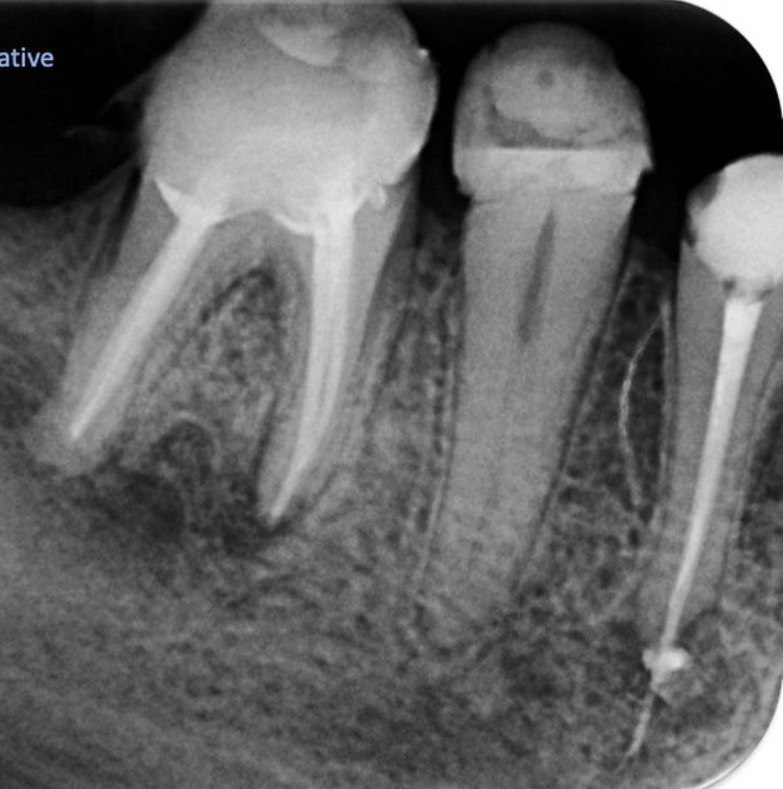

5. What Condition can be seen in this X ray regarding the tooth # 4.6?

6.What Condition can be seen in this X ray regarding the tooth # 4.6?